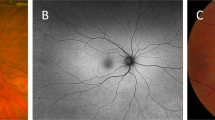

The study was performed using a Heidelberg SD-OCT instrument (Heidelberg Engineering Inc., Heidelberg, Germany). First, it was determined that the scanning site was the B zone. Morphologically, the characteristics of the blood vessels in zone B are more in line with the description of small arteries and venules. Second, after the retinal blood vessels are emitted from the centre of the optic disc, there is less arteriovenous crossing and pulsation of the retinal artery in the B area, far from the optic disc. Measurement of the retinal arteriovenous diameter was not affected. The scan was completed before the vessel branching in the B zone region. If the blood vessel had branched before the B zone, it was scanned before it branched (Fig. 1). After the scan was completed, the vertical: horizontal ratio of the obtained OCT image was adjusted to 1:1 μm and enlarged to 800%, and the OCT image screenshot in the BMP image format was saved. Only the image showing the blood vessel wall could be selected for the next study. At least 5 clear OCT images were scanned for each blood vessel for analysis. We found through previous studies4 that different forms of retinal blood vessels can be obtained using different scanning methods (Fig. 2).

A concentric circle is drawn on transparent plastic film to determine the B area. According to the magnification of the fundus image on SD-OCT, the centre circle determines the diameter of the optic disc. Then, two concentric circles are drawn with one disc diameter and 1.5 disc diameters. The second circle and the third circle are in the B area. The blood vessels in zone B are scanned. The plastic film is attached with the positioning ring to the computer screen. The position is attached to the centre of the optic disc. The position of the B area is determined, and the blood vessels in the area are scanned.

When the scan line coincides with the supraorbital retinal artery and vein, the image shows that the corresponding retinal blood vessels start from the optic disc and are located between the nerve fibre layer and the inner striate layer, and the upper and lower vessel wall structures are visible. When the scan line is perpendicular to the blood vessel, the cross-sectional structure of the retinal blood vessel can be obtained, and the upper and lower wall structures of the blood vessel and the blood flow image of the lumen are displayed. When the scanning line is not perpendicular to the blood vessel, the retinal vascular structure is blurred, and the image of the blood vessel wall is unclear. When the scan line is perpendicular to the blood vessel, the wall structure of the blood vessel is clearer than before. When a circular scan is used to scan the retinal arteries and veins of each quadrant, part of the vascular structure is not clearly displayed, and the linear structure is clearer than the circular scan.